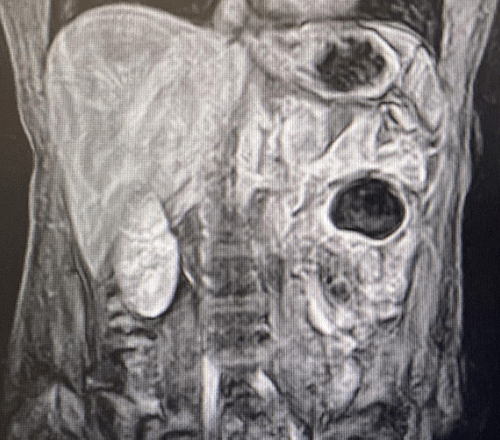

On admission, the patient was afebrile, normotensive, and in no respiratory distress, with oxygen saturation of 97% but was tachycardic to 105. Physical examination revealed a well-developed woman who appeared her stated age. The patient had a soft, nondistended, diffusely tender abdomen without rebound, guarding, or evidence of trauma. A complete blood count revealed a leukocytosis of 13.9 with a normal comprehensive metabolic panel. After a clinical exam and complete workup, the patient was thought to have a small bowel obstruction. With an inconclusive ultrasound (USG), she underwent radiographic evaluation via computed tomography (CT) imaging (Figure 1). CT revealed a LUQ mesenteric fat attenuating mass with mild adjacent mesenteric edema. A magnetic resonance imaging (MRI) was obtained (Figure 2) to evaluate the mass better, including the localization and features of the tissue, revealing an approximate 5 × 4 × 4 cm jejunal mesenteric mass most consistent with a mature cystic teratoma, with induration of surrounding mesentery.

Figure 1. CT of Abdomen and Pelvis Demonstrating LUQ Mesenteric Fat-Containing Mass. Published With Permission